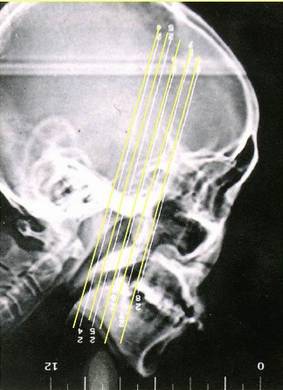

- 副鼻窦X线检查,CT(冠状位、轴位)检查已常规应用。

正常鼻窦CT

鼻窦炎轴位CT

鼻窦炎冠状CT